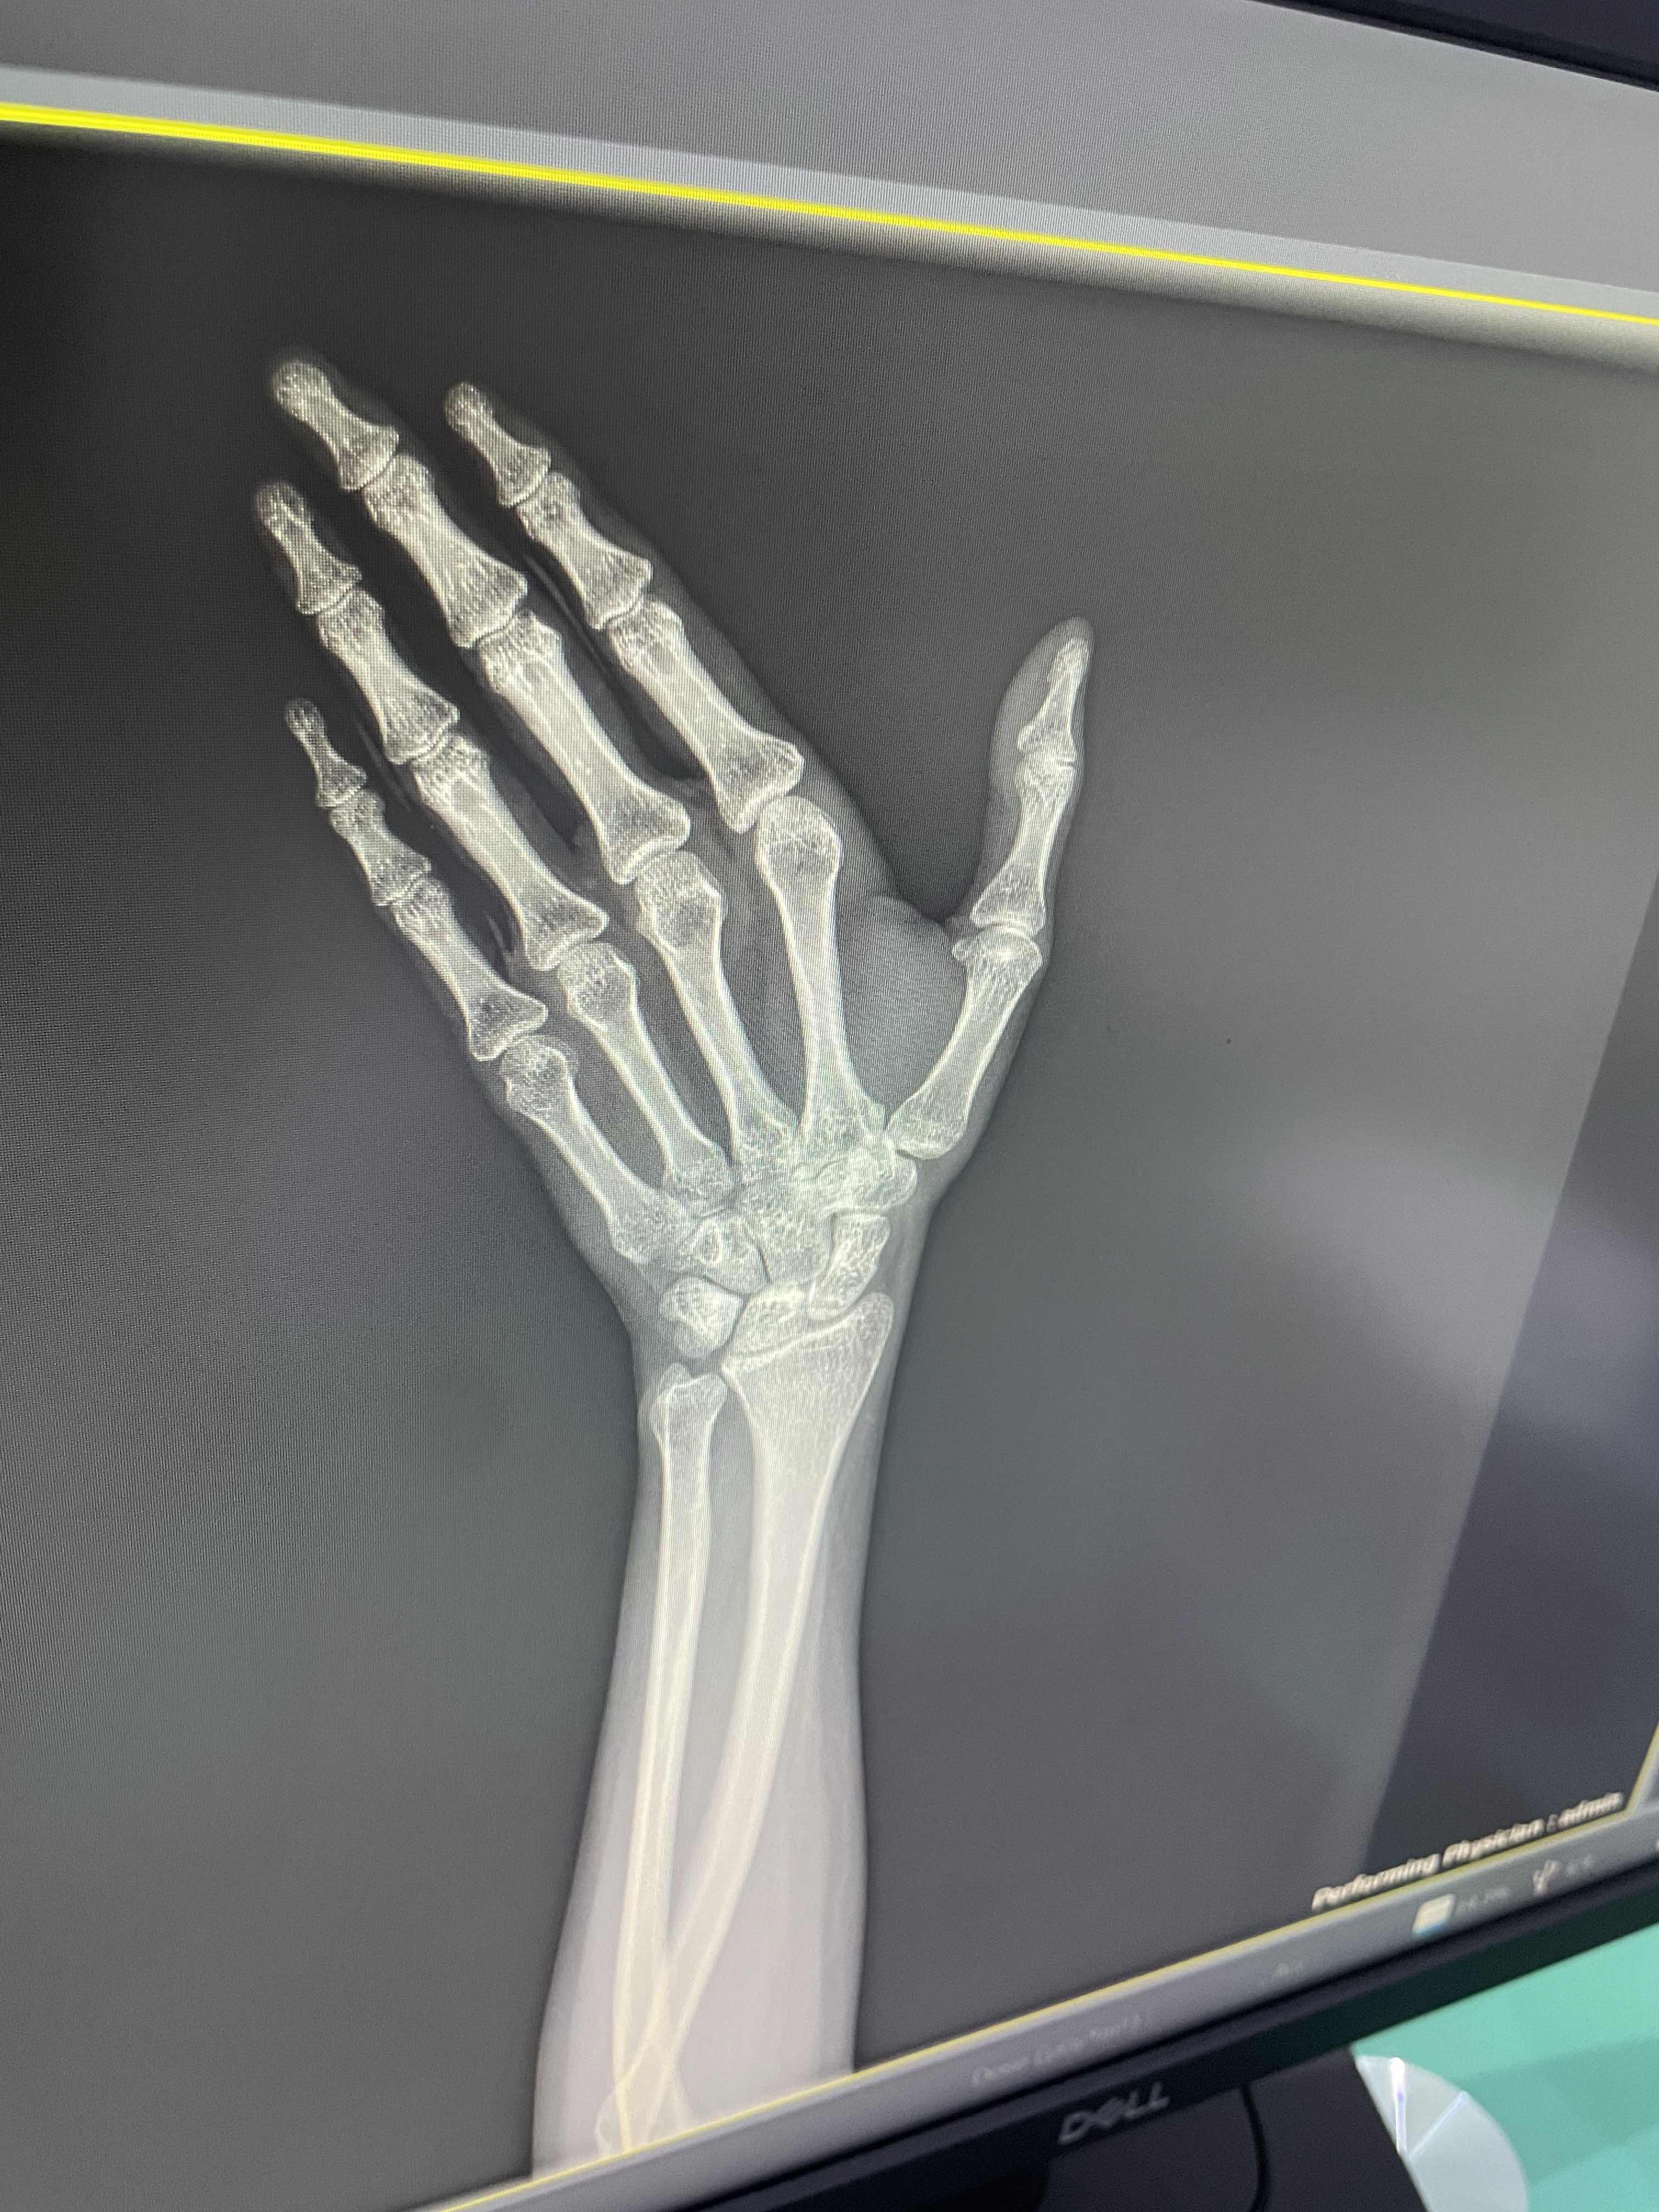

هل يوجد كسر وتمزق باوتار اليد

هل يوجد كسر وتمزق باوتار اليد ١٢ يوم من يوم الطيحه ٩ ايام من يوم ركبت الجبس الاعراض قبل اركب الجبس ورم ب المفصل ولون المفصل ازرق بس ما في الم فيه الا اذا لفيت يدي او شديت عليها